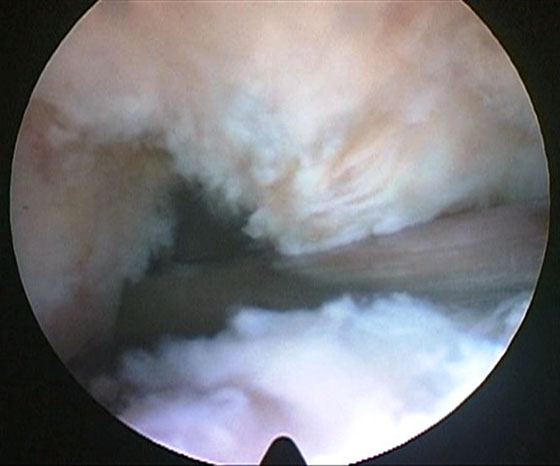

Las lesiones del LCP pueden ser aisladas o combinadas. Las combinadas en general como parte de una luxación de rodilla obvia u oculta. A su vez las lesiones las clasificamos en agudas, subagudas o crónicas. Arbitrariamente tomaremos las lesiones como agudas hasta las 6 semanas, subagudas hasta los 6 meses y crónicas con más de 6 meses. Este concepto no tiene directa relación con los términos habituales, pero en las lesiones del LCP, y fundamentalmente en las combinadas, donde hay que observar varios parámetros, como las lesiones asociadas, ya sean multiorgánicas o las neurovasculares del miembro afectado, los tiempos para resolver la patología deben evaluarse cuidadosamente y suelen demorarse. Dentro de este esquema buscamos poder realizar la cirugía lo más rápido posible para aprovechar al máximo el escenario inflamatorio que nos proporciona la lesión aguda y la estructura de “andamio” de las fibras remanentes para lograr una mejor integración del injerto manteniendo su estructura y longitud (Fig.1). En la práctica difícilmente podamos realizar la cirugía en estos pacientes antes de las 3 semanas del trauma, y nos extendemos hasta los 6 meses porque creemos que todavía los fenómenos de elongación no se han producido o son mínimos.

Figura 1